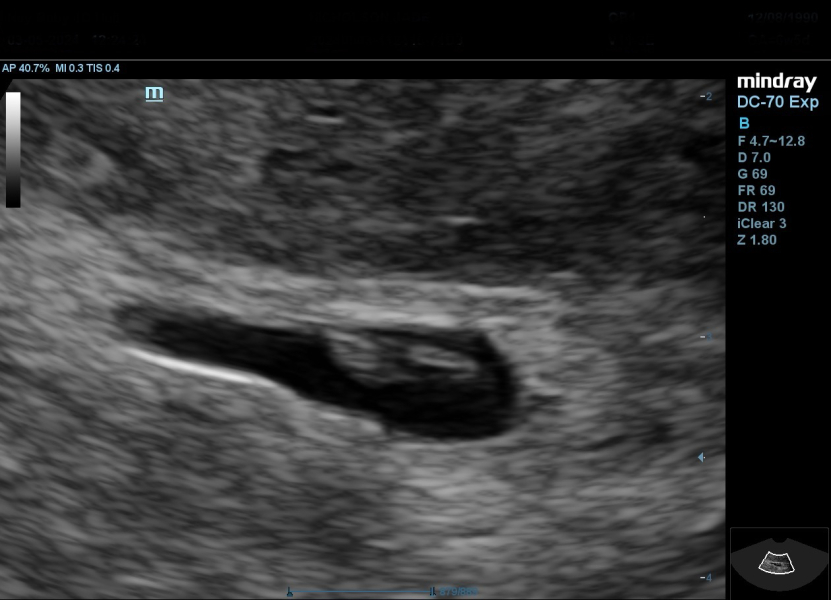

Hi ladies, Iv been a bit quiet on here but starting to get a little more hope and positivity. Due to multiple miscarriages I had a scan at what I thought I was 6w. They saw yolk sac and gest sac and dated me at 5w. Just had a private scan before my next NHS check up as I was so anxious and I saw little baby and heartbeat. Measuring 6w 3d. I'm re assured, for now! 🥰

Thank you so much @Hopingrae, your message made me book a scan this afternoon and thank goodness everything is still ok. I feel relieved but know it will only last a few days before the worry sets in again!